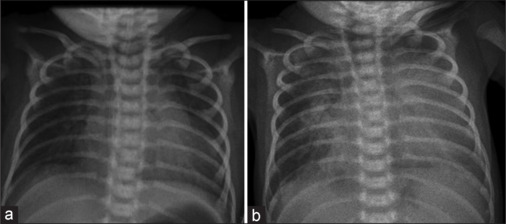

We describe a 7-day-old newborn who presented with arterial desaturation and respiratory distress. The evaluation showed a duct with a continuous right-to-left shunt and an anomalous origin of the right pulmonary artery from the aorta. We discuss the hemodynamics leading to continuous right-to-left ductal flow and the subsequent intraoperative evaluation that resulted in a successful single-stage surgical repair of this interesting case.